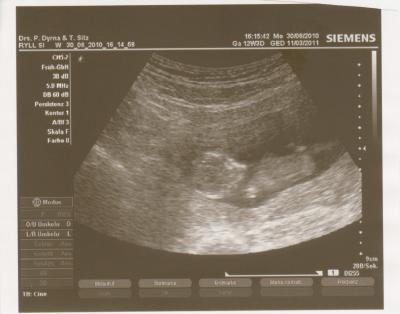

Mit unserem kleinen Schatz ist alles in Ordnung. Es ist nun 6,1cm groß und hat wie wild getobt, dadurch konnte der FA keine Nackenfalte messen aber das ist wohl nicht schlimm, sah nicht auffällig aus. Es war so toll das mein Schatz dabei war, er fand das auch unbeschreiblich toll. Und ich habe meine erste Blutabnahme heil überstanden war wirklich halb so schlimm, bin jetzt abgehärtet Habe gleich Toxoplasmose und CMV-Test mitgemacht, kostet mich etwas über 40€. Aber besser ist mal, wir haben ja auch ein Katerchen. Und endlich habe ich meinen MuPa bekommen!!! @smily-tina mein nächster Termin ist der 27.09.2010 und da könnte man wohl vielleicht schon sehen was es wird da bin ich aufgeregt! So und nun noch ein Bildchen von meinem Schätzchen (muss nun für jedes Bildchen immer 1,50€ bezahlen) Liebe Grüße von mimi SSW von 12+6 auf 12+5 gestuft, also Mittwoch 'erst' 14.SSW

Bild zu Ich bin wieder da und verdammt glücklich :-) - Forum für März - Mamis